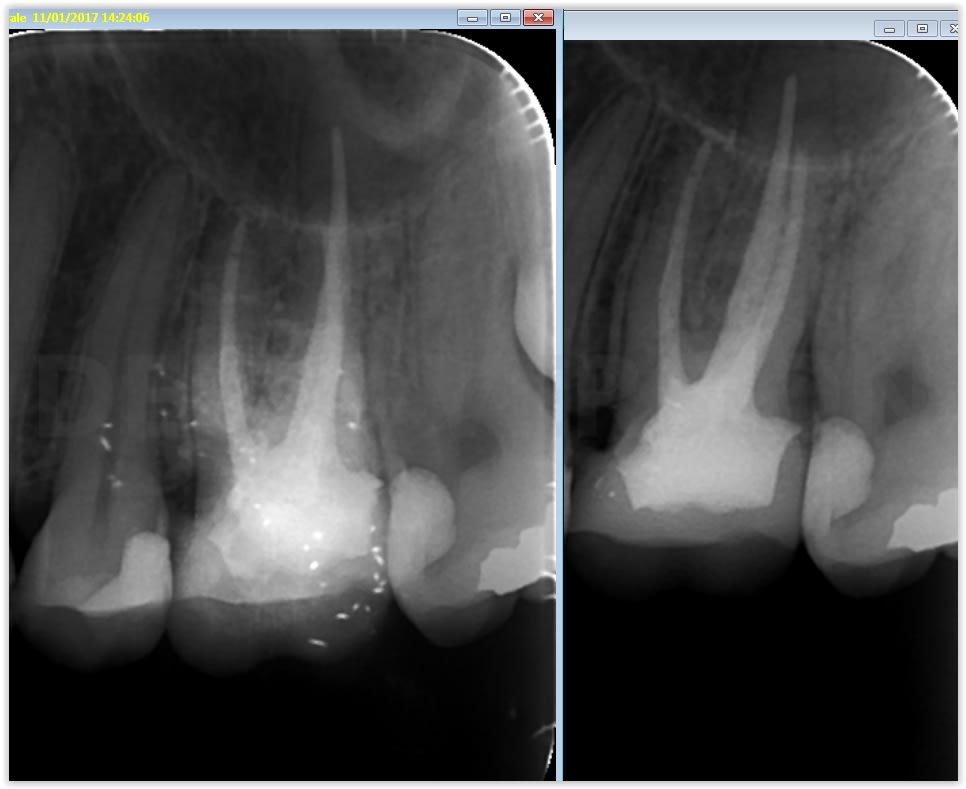

J'ai reçu la Camera intrabuccale 1/4 Sony CCD MD960u ce matin. Pas encore eu trop le temps de me pencher sur les réglage, mais voici ce que ça donne une fois installée et branchée...

Je trouve cela pas mal du tout pour une camera à 200€! :-)

Beaucoup mieux que la MD740, non?

Quelques photos prises ce matin au cours d'une longue séance de soins. Je posterais un test complet de la caméra bientôt pour ceux que ça intéresse...